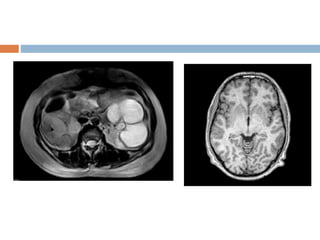

Chemical shift artifact

 In the frequency direction, the MR scanner uses

the frequency of the signal to indicate spatial

resolution

 Since water in organs and muscles resonate at

different frequency than fat.

 The MR scanner mistakes the frequency as a

spatial difference.

 Commonly noticed in vertebral end plates,

abdomen, and orbits where fat and other tissues

form borders.

 Water protons frequency 3.5 ppm precess at

 Appearance

 Spine -one end plate to appear thicker than

the opposite one.

 Abdomen &orbits -Black border at fat water

interfaces and bright border at opposite

border.

 Solution

fat suppression technique

Use wide receiver bandwidth

Chemical shift artifact In the frequency direction, the MR scanner uses the frequency of the signal to indicate spatial resolution  Since water in organs and muscles resonate at different frequency than fat.  The MR scanner mistakes the frequency as a spatial difference.  Commonly noticed in vertebral end plates, abdomen, and orbits where fat and other tissues form borders.  Water protons frequency 3.5 ppm precess at

 Appearance  Spine-one end plate to appear thicker than the opposite one.  Abdomen &orbits -Black border at fat water interfaces and bright border at opposite border.  Solution fat suppression technique Use wide receiver bandwidth